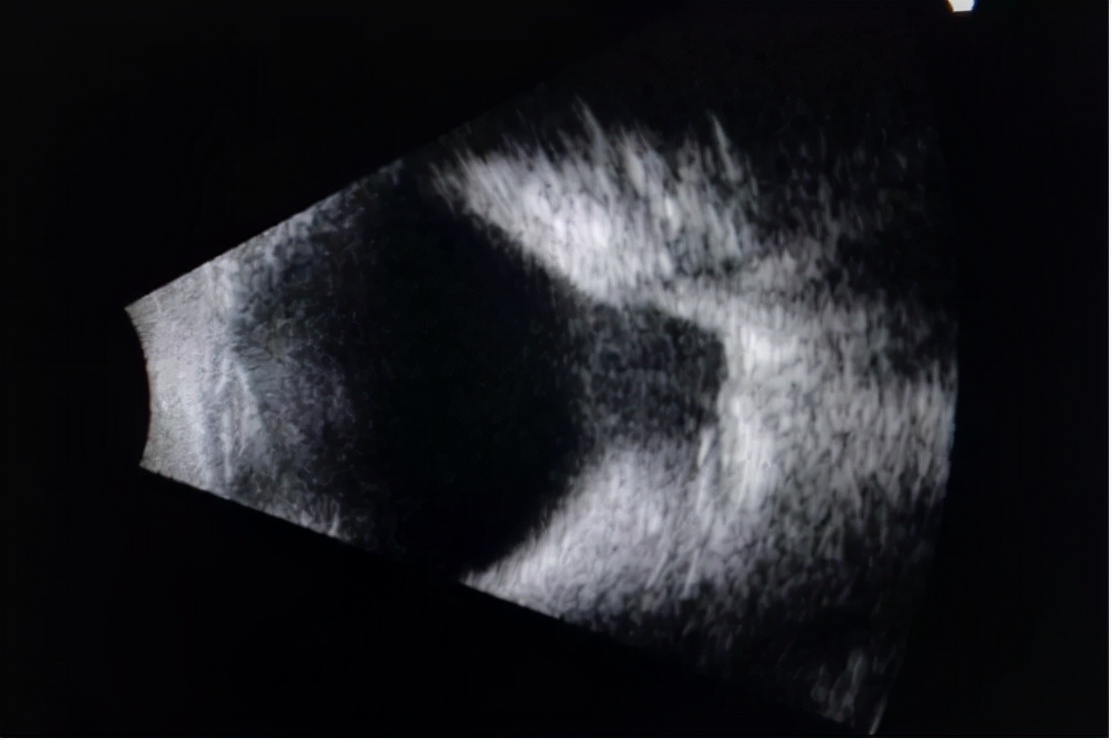

后巩膜葡萄肿

眼轴拉得越长,眼球壁各层越向后扩张,后部巩膜,特别是黄斑部和视盘周围巩膜明显变薄,眼球后部呈蛋形膨出, 形成后巩膜葡萄肿 。